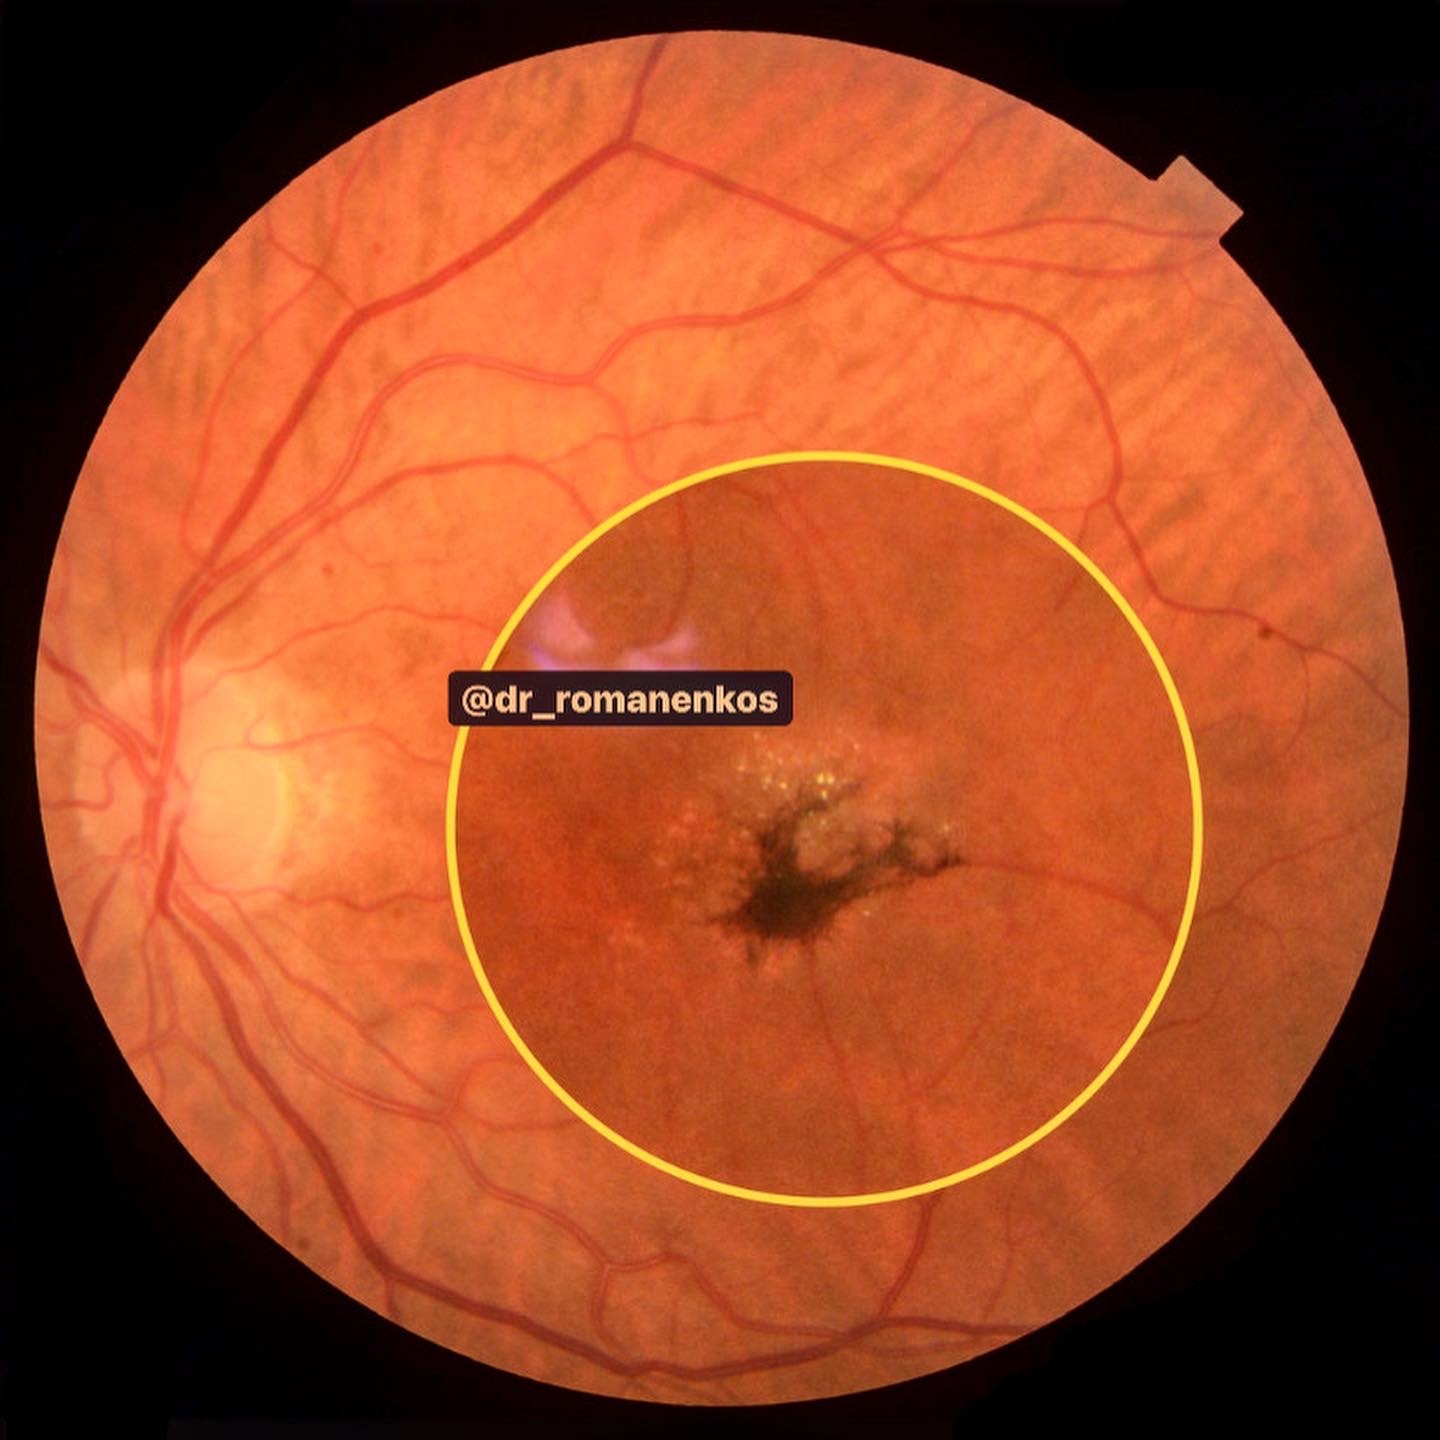

- все материалы (фото фундус камеры, сканы ОКТ взяты из личной практики и разобраны для Вас лично мной) - это ЧЕСТНО! А здесь только так!

- видео, сканы ОКТ с обозначениями, фото глазного с разбором на детали, аудисопровождение, текст и, конечно, ОБУЧАЩИЕ ТЕСТЫ